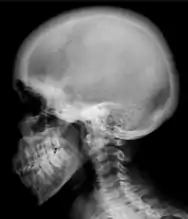

Ground glass density of the skull.[18]